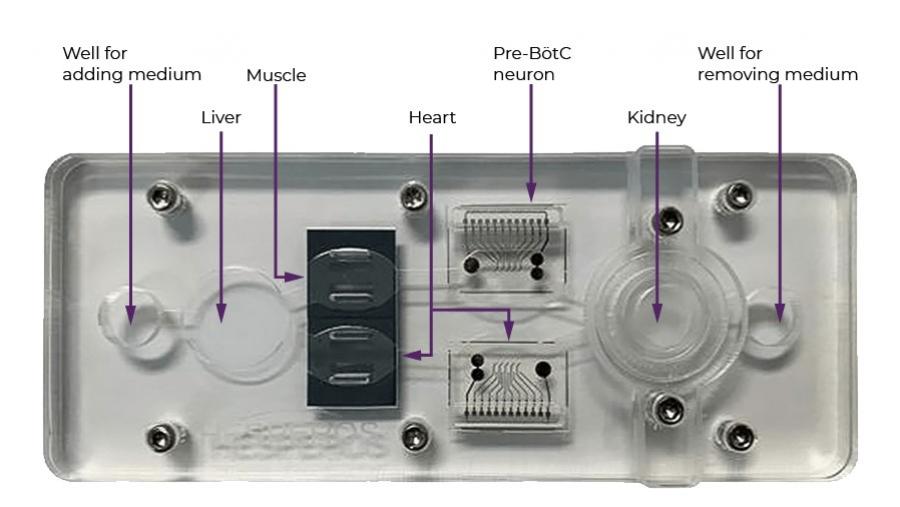

Tissue chip-based model screens potential pain medications faster

Published: December 10, 2021

Topics:

New Drugs/Screening Tools

With new technology, researchers can understand the effects of repeated overdoses and test new treatments.

Published: July 16, 2020

Topics:

New Drugs/Screening Tools